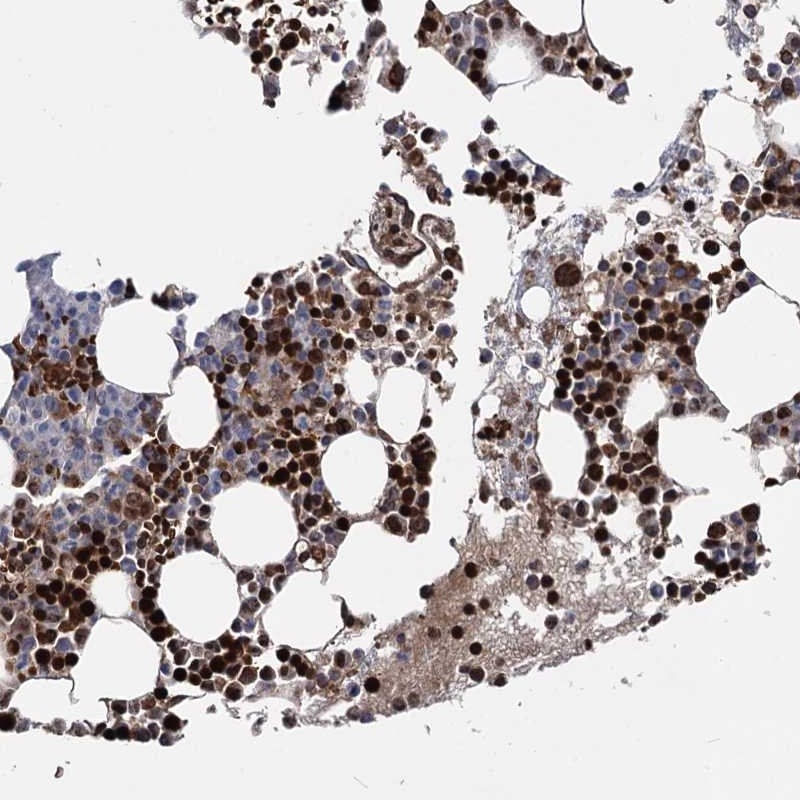

Immunohistochemical staining of human bone marrow shows strong nuclear positivity in bone marrow poietic cells.